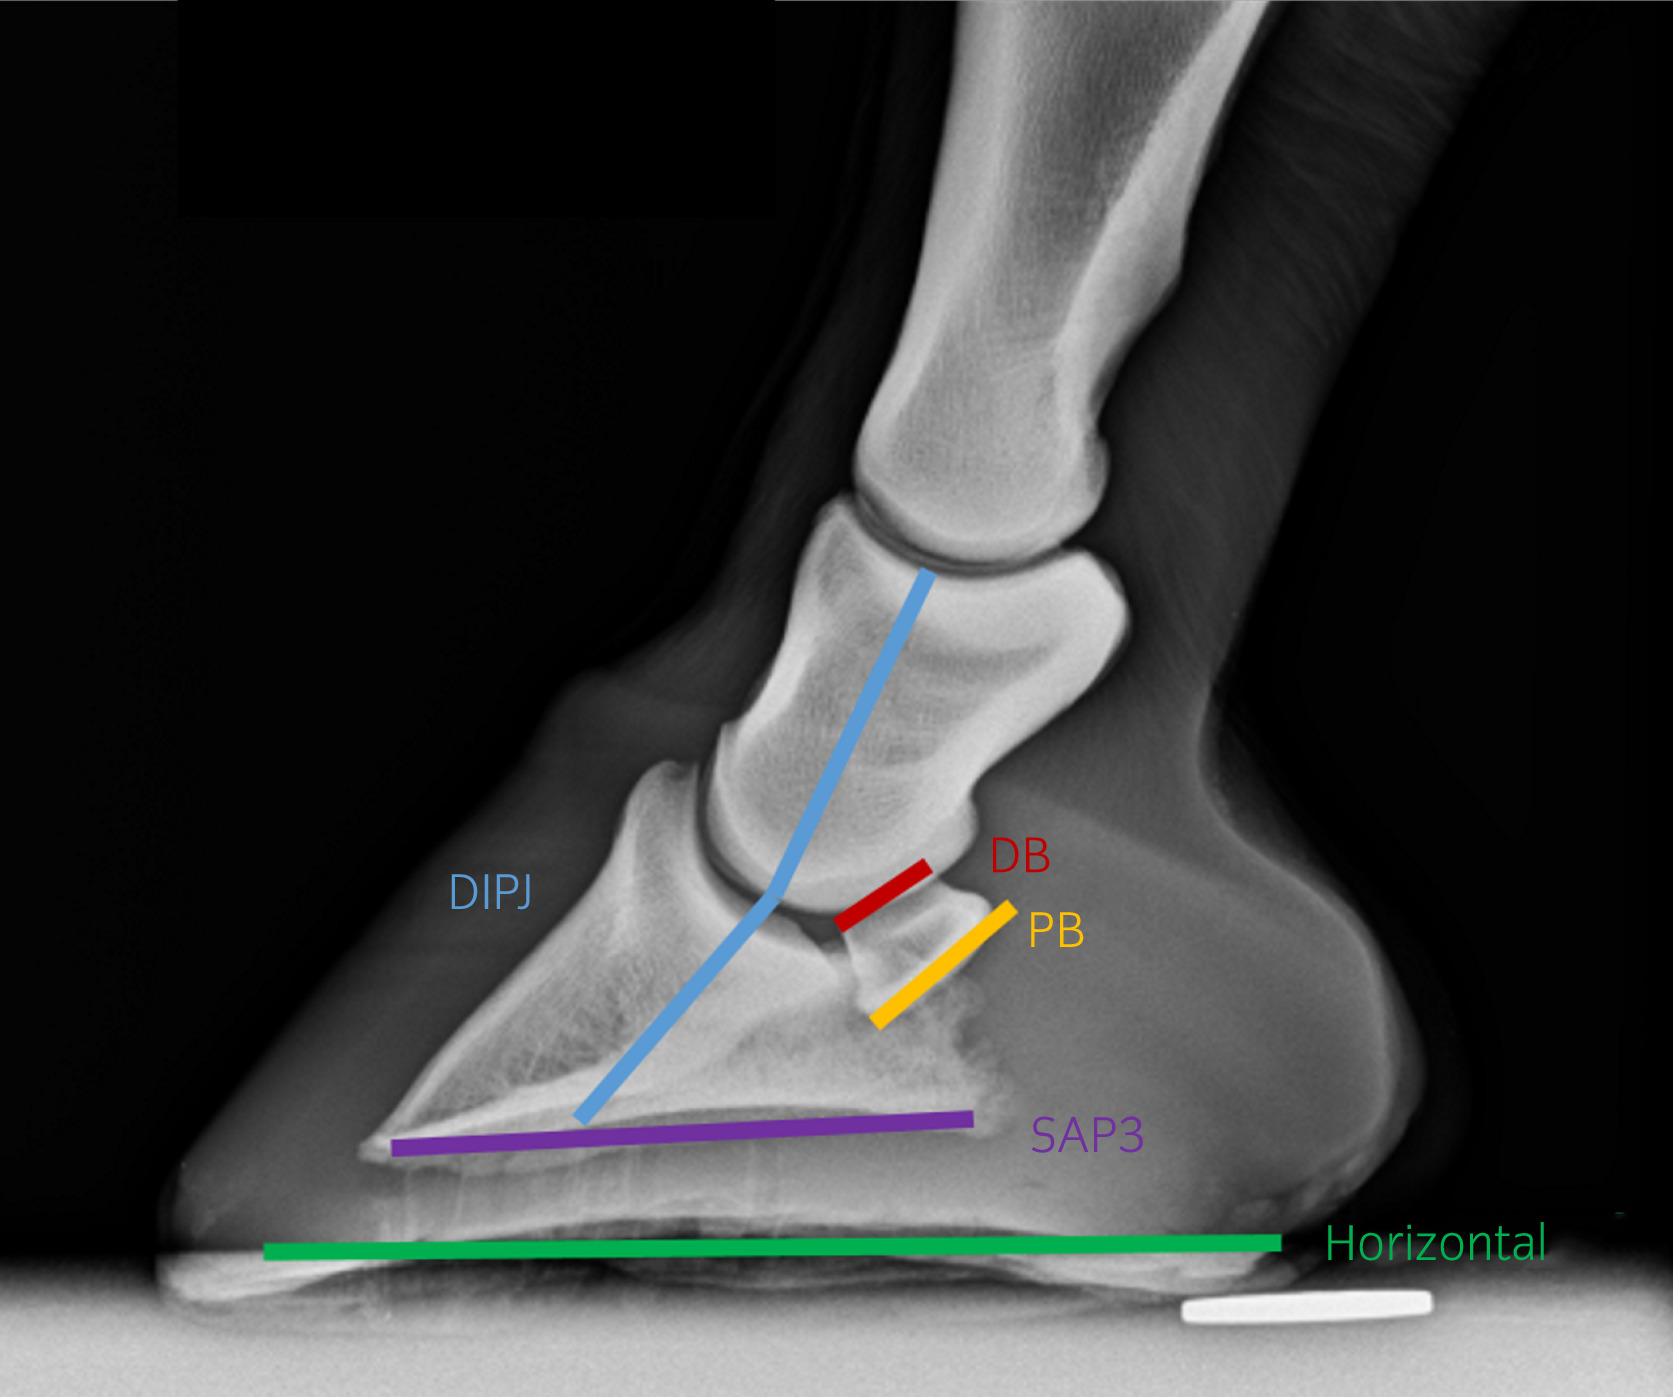

The navicular bone sits deep within the hoof, positioned between the deep digital flexor tendon (DDFT) and the coffin joint. It plays a crucial biomechanical role in force transmission, shock absorption, and movement efficiency.

Corrective farriery remains the cornerstone of navicular management. The goal is biomechanical: reduce stress on the navicular region, improve breakover, optimise loading patterns, and support healthy hoof function.